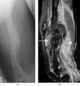

Soft-tissue deformity

Haglund's syndrome is a group of signs and symptoms consisting of Haglund's deformity (which is an exostosis of the posterior calcaneal tuberosity) in combination with retrocalcaneal bursitis. It is often accompanied by Achilles tendinitis.Haglund's deformity typically presents with a prominent bump on the upper posterior calcaneus. [Source: Wikipedia ]